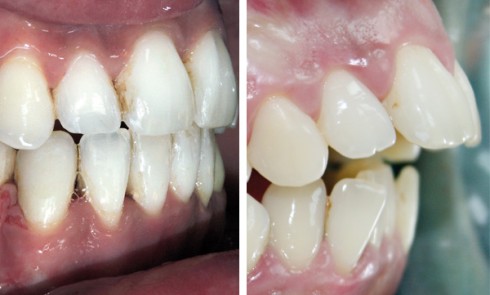

Examen clinique À l’examen exobuccal, le visage est ovalaire, les étages de la face sont équilibrés. Le profil général est...

ODF

Article réservé à nos abonnés Apport des nouvelles techniques chirurgicales dans notre prise en charge

Mme M. présente une classe II squelettique par rétrognathie mandibulaire dans un contexte vertical hyperdivergent sévère se traduisant par un profil...